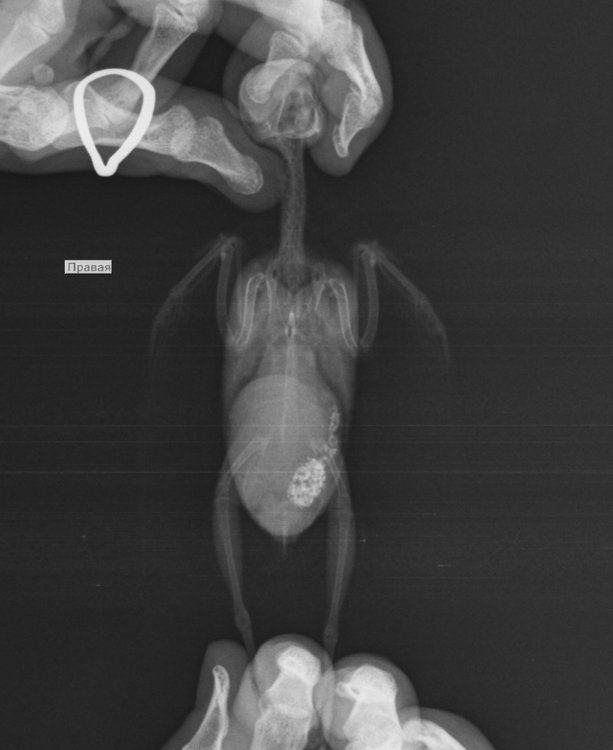

У волнистика неоплазия почки (не исключена киста), бактериальный энтерит

Попугай болен, опухоль, у Кеши изменился стул, стал водянистым, иногда вместо стула были белые лужицы. Он стал немного вялым. Стала давать Ветом 1.1, Бифтрилак. Далее симптомы усугубились, он стал просиживать в клетке, нахохлившись, потом появилась дрожь. Он перестал чирикать. Я заподозрила отравление. Посетили прием врача-орнитолога, сделали анализ помета и рентген. Анализ помета показал, что есть небольшое воспаление. Рентген показал наличие большой опухоли. Прописали поддерживающее лечение, Мелкосидил, амоксиклав суспензия 250, нистатин, гепатовет. Оно не помогает. Сейчас он так же сидит нахохлившись и дрожит, дышит тяжело, закрывает глазки, словно ему больно смотреть, иногда поджимает лапку, кушает в меру. Я понимаю, что у нас мало шансов, но может посоветуете какое нибудь противоопухолевое лечение.

Масса попугайчика 35 грамм. Он похудел очень, хотя кушает неплохо. врач сказала, что надежды для нас нет. Мы сейчас будем пить ибупрофен и мелкосидил. Делаю ингаляции с эуфиллином и корвалолом.